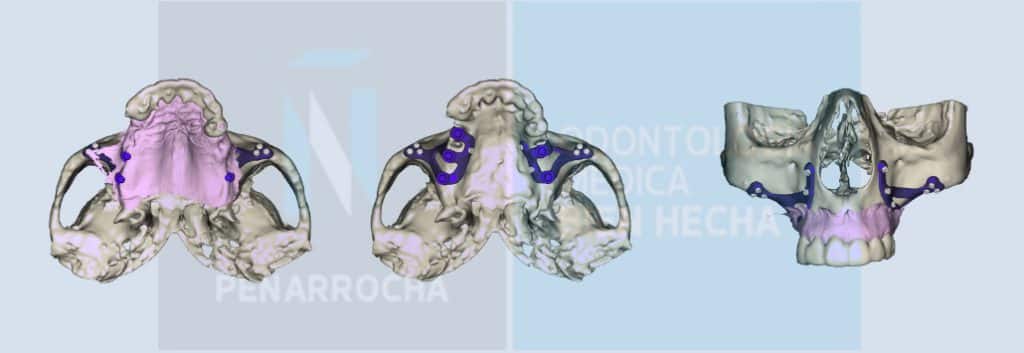

Endodoncia mal hecha: síntomas, causas y qué puedes hacer

¿Te han hecho una endodoncia y notas que algo no va bien? Este tratamiento se realiza con el fin de evitar la pérdida de un diente con caries que está muy dañado. Aunque cada vez se realizan mejores endodoncias y técnicamente están bien hechas, se calcula que el fracaso de una endodoncia oscila entre el 2 […]